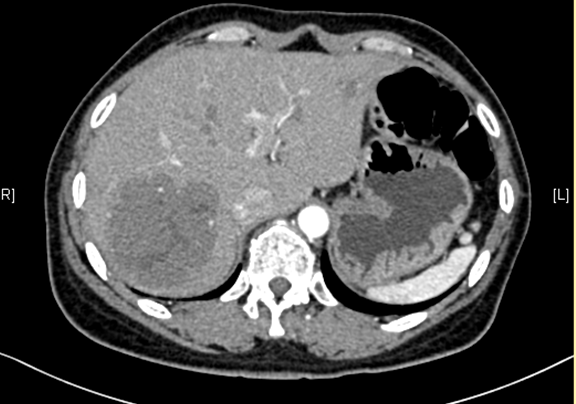

辅助检查: 下腹部增强CT示:考虑肝脏多发血管瘤可能性大。

术前CT检查:动脉期

静脉期

平衡期